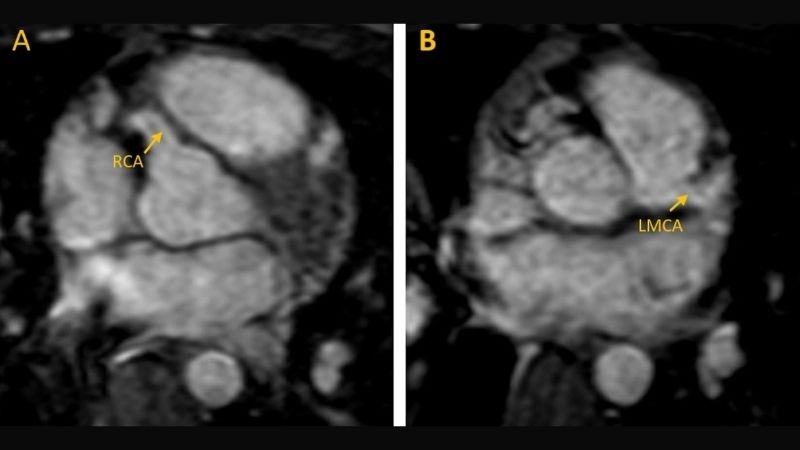

Images visual examples of Anomalous Left Coronary Artery From The Pulmonary Artery (ALCAPA)

Images often illustrate how the left coronary artery abnormally arises from the pulmonary artery instead of the aorta, showing blood flow disruptions and oxygen supply issues in the heart muscle.